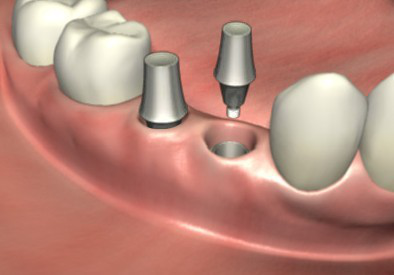

3、安装愈合基台使种植体穿出牙龈,等待2~3周让软组织成形。

4、软组织成形后用永久基台换下愈合基台,较后安装固定种植牙冠便完成了种植牙手术。